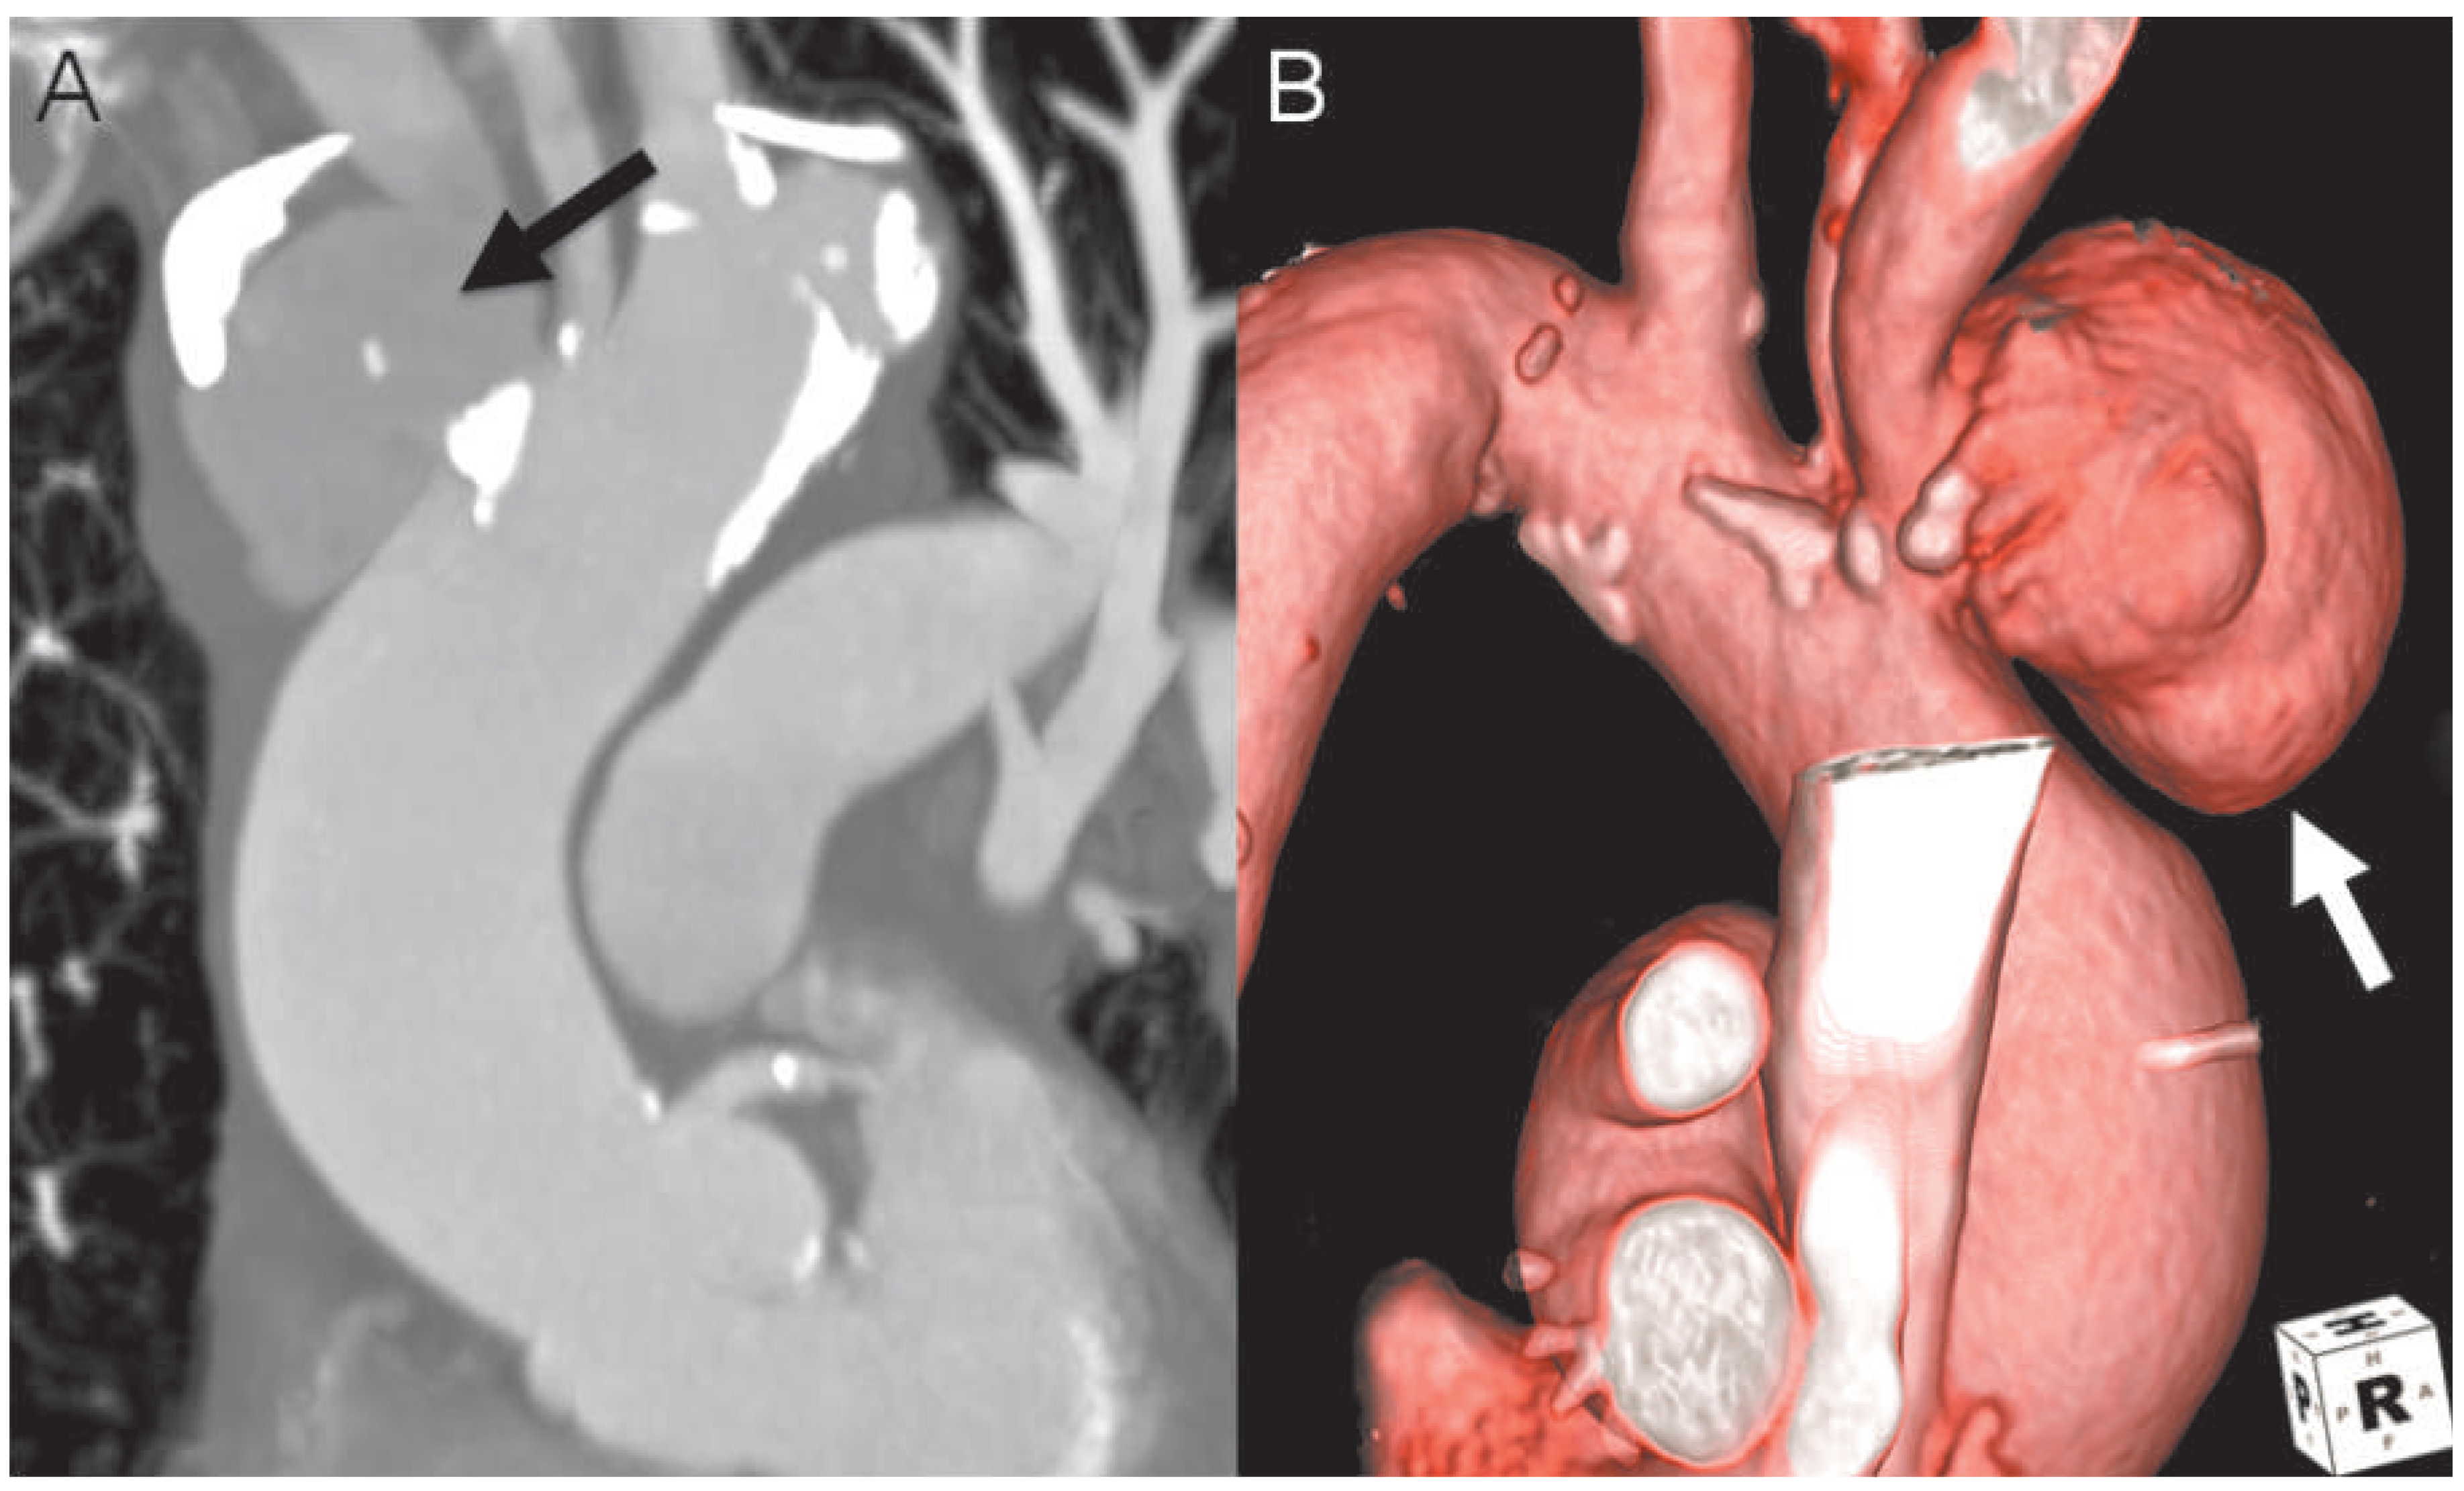

Simple Repair Technique for Rupture of the Brachiocephalic Trunk